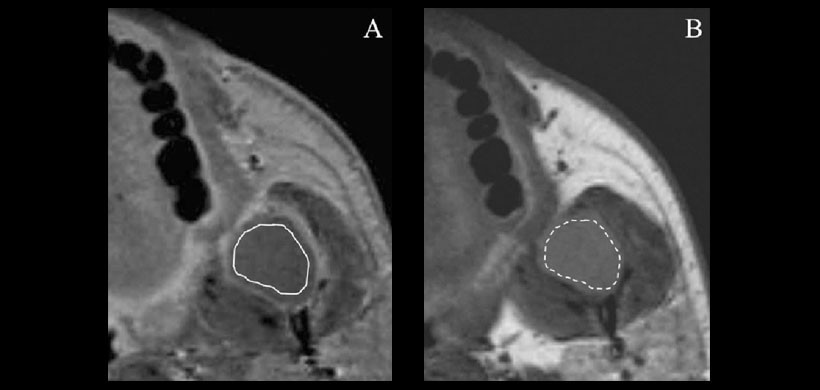

Figura 1: Ameloblastoma de la rama mandibular izquierda en un varón de 41 años. (A) La región de interés (ROI, línea continua), que evitó la zona periférica mejorada, se dibujó en una imagen ponderada T1 (T1WI) con contraste aumentado (CE). (B) El ROI (línea discontinua) fue copiado de la Resonancia con contraste mejorado.